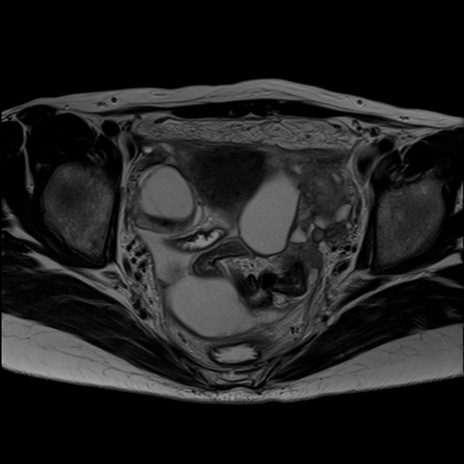

症例39 T2WI(横断像)

MRI(4日後)